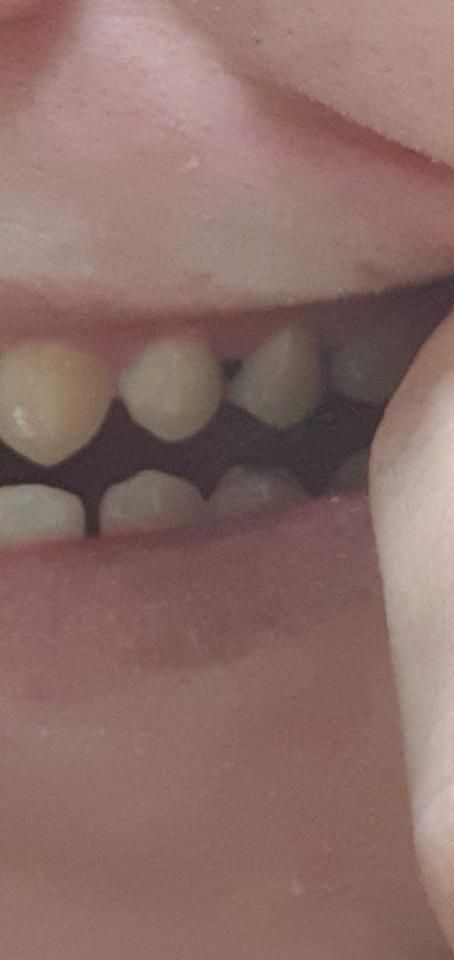

• 2번 째 사진